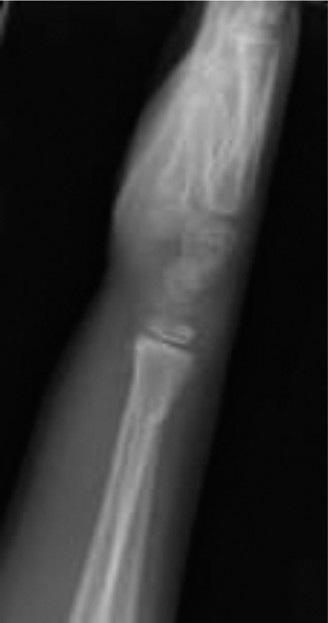

Standard orthopedic trauma radiographic evaluation of the left wrist was obtained, comprising orthogonal posteroanterior, lateral, and oblique projections. Accurate radiographic interpretation requires careful analysis of the fracture geometry, the degree of displacement, and the integrity of adjacent anatomical structures.

The initial posteroanterior projection demonstrated a transverse fracture line propagating through the distal metaphysis of the radius. The fracture line extended proximally from the radial cortex and exited through the physis on the ulnar side.

This specific propagation pattern is the hallmark of a Salter-Harris Type II fracture. There was significant dorsal displacement of the distal epiphyseal-metaphyseal fragment relative to the proximal radial shaft. The lateral radiograph provided critical information regarding the sagittal plane deformity.

The lateral view confirmed the Salter-Harris Type II classification, revealing marked dorsal displacement and an apex volar angulation measuring approximately 35 degrees. Furthermore, there was significant overriding of the fracture fragments, with approximately 75% dorsal cortical translation.

An additional oblique view was obtained to further delineate the metaphyseal component and assess for intra-articular extension or occult carpal pathology.

The oblique projection clearly highlighted the "Thurston Holland fragment." This is the pathognomonic triangular metaphyseal fragment that remains attached to the epiphysis on the compression side of the injury. The presence of this fragment confirms that the fracture line has exited through the metaphysis rather than traversing the entire physis (which would be a Salter-Harris Type I) or entering the epiphysis and joint space (Salter-Harris Type III or IV).

The distal radioulnar joint appeared radiographically congruent on all views, with no evidence of an associated ulnar shaft fracture, ulnar styloid avulsion, or widening of the radioulnar interval. The carpal arcs of Gilula were intact, and the growth plate of the distal ulna appeared uninjured.